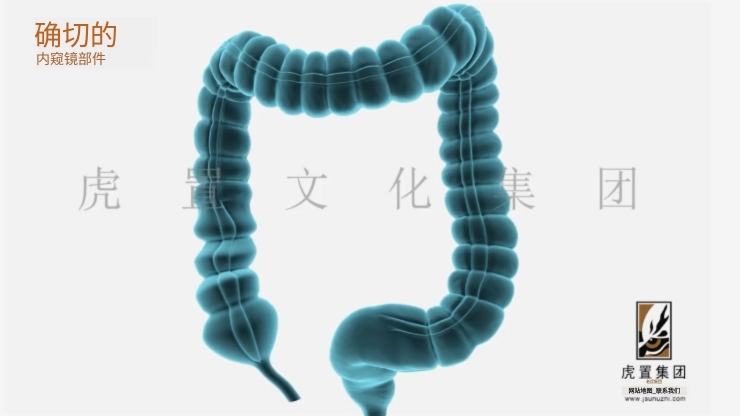

深耕于数字设计及展示领域的虎置文化集团正努力成为全球知名的数字设计及展示服务商,创办至今20年,旗下五家子公司,是集设计、展示、施工于一体的综合运营服务商。集团旗下控股上海虎置文化集团有限公司、江苏虎置文化传播有限公司、上海比筑视觉艺术设计有限公司、上海虎置建筑设计有限公司和江苏艺派数字科技有限公司四家子公司,为不同行业客户提供基于文化创意服务的整体解决方案。

致力于:全案设计、展馆展厅、三维动画、卡通动漫、影视广告、3D效果图等综合服务,设计包括:建筑设计、景观设计、规划设计、展馆设计、室内设计、 BIM设计;展示包括:三维动画、全息展示、影视广告、数字展馆、二维动漫、3D仿真效果图、VR&AR等;施工包括:展馆展厅、室内装饰、幕墙工程、亮化工程。